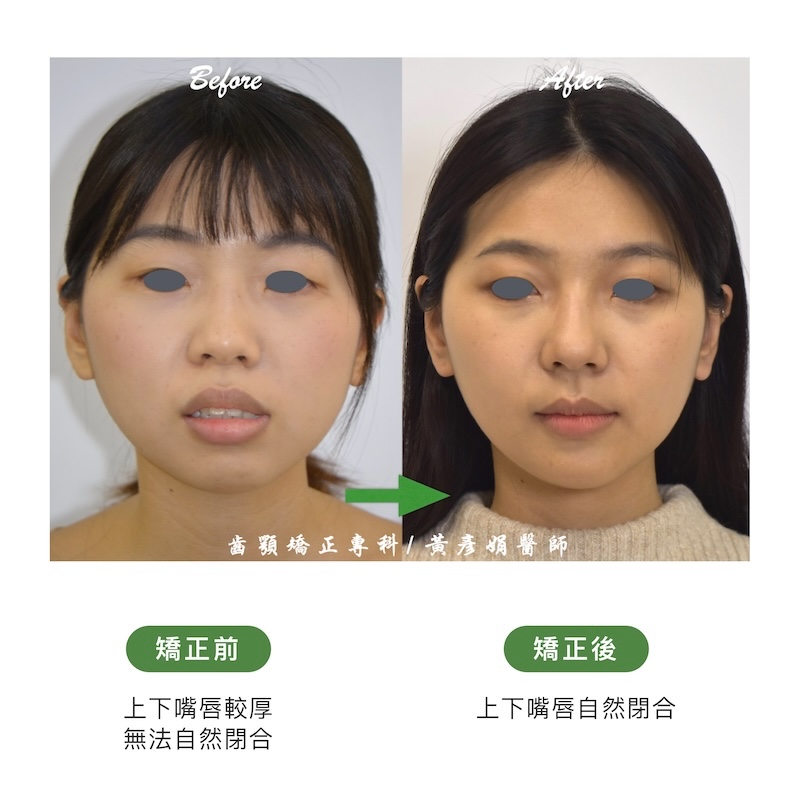

牙齒矯正前:骨暴/暴牙/嘴唇閉不起來/牙齒凌亂/牙齒擁擠

- 主訴:暴牙、嘴唇閉不起來、牙齒亂

牙齒矯正前後臉型外觀變化

謝謝佩佩在兩年半的矯正過程當中,一直保持刷牙很乾淨和認真戴橡皮筋,看著牙齒越來越整齊、笑起來越來越美,真的很有成就感!